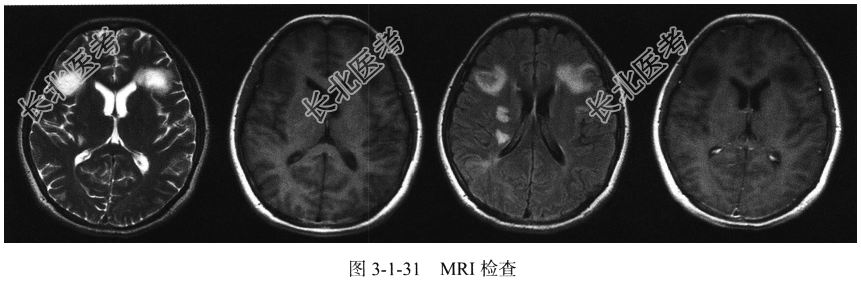

- [材料题] 患者,女,14岁,癫痫发作,1周前发热,体温39℃,于当地治疗后缓解(图3-1-31)。

- 简答题1、该患者MRI检查有何异常改变?

- 简答题2、患者可能诊断为什么?